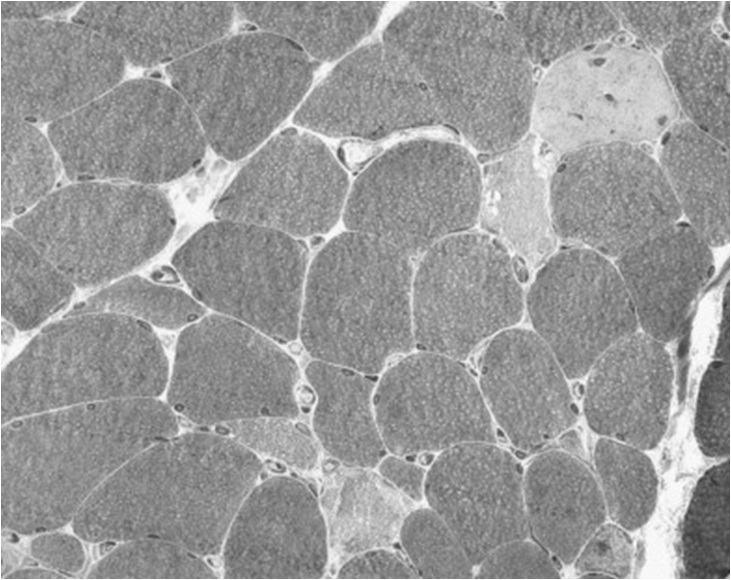

Subtypes of Critical Illness Myopathy: Minimal Change Myopathy

The first subtype is minimal change myopathy. There is increased fibre size variation, some appearing atrophic and angulated as they become distorted by their normal neighbours. Type II fibre involvement may predominate, perhaps because fast twitch fibres are more susceptible to fatigue and disuse atrophy. There is no inflammatory response and thus serum creatine kinase is normal.

Clinically, it may be apparent only as an unexpected difficulty weaning from ventilation, and the EMG changes may be mild, making muscle biopsy more critical.

The condition may lie on a continuum with disuse atrophy, but made more extreme by a severe catabolic reaction induced by sepsis and systemic inflammatory responses triggering multi-organ failure (Schweickert & Hall, 2007). Muscle is one such target organ; ischaemia and electrolyte and osmotic disturbance in the critically ill patient trigger catabolism by releasing glucocorticoids and cytokines such as interleukins and tumour necrosis factor. For example, Interleukin 6 promotes a high affinity binding protein for insulin like growth factor (IGF) to down-regulate the latter and thereby block its role in glucose uptake and protein synthesis. This is paralleled by a state of insulin resistance. Muscle may be particularly susceptible to catabolic breakdown, being a ready “reserve” for amino acids to be used in proteolysis to maintain gluconeogenesis for other vital tissues in the body’s stressed state (Van den Berghe, 2000). A starved patient may lose around 75 g/day of protein, while a critically ill patient may lose up to 250 g/day, equivalent to nearly 1 kg of muscle mass (Burnham et al., 2003). Disuse, exacerbated iatrogenically by sedatives, membrane stabilisers and neuromuscular blocking drugs, may impair the transmission of myotrophic factors and further potentiate the tendency to muscle atrophy (Ferrando, 2000).